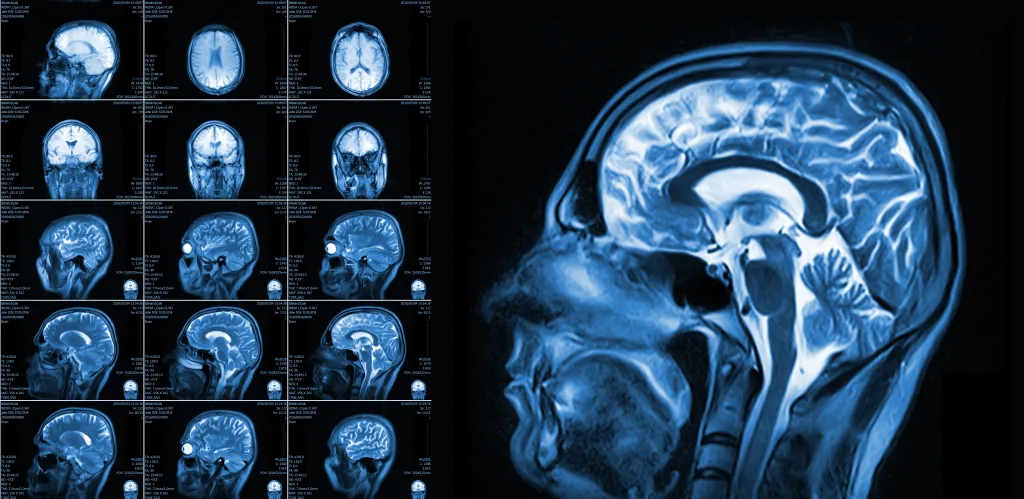

The volunteers underwent tests at the start, midway through, and at the end of the trial. At each visit, blood pressure and body composition were measured, and in the final round they added cognitive tests and advanced imaging to track blood flow to their brains.

By the end of the study, the brain-boosting benefits were clear. Imaging tests showed a significant improvement in brain vascular responsiveness, or the ability of their blood vessels to widen and constrict to regulate blood flow.

After 16 weeks of peanut consumption, participants’ global cerebral blood flow (CBF) increased by 3.6% compared with the control period.

When Joris and his colleagues examined the participants’ brain gray matter, home to the cell bodies of the brain’s neurons, they found blood flow had increased by 4.5%.

The frontal lobes experienced a 6.6% boost, while the temporal lobes rose 4.9%. These regions play key roles in memory, language, decision-making and emotional control.